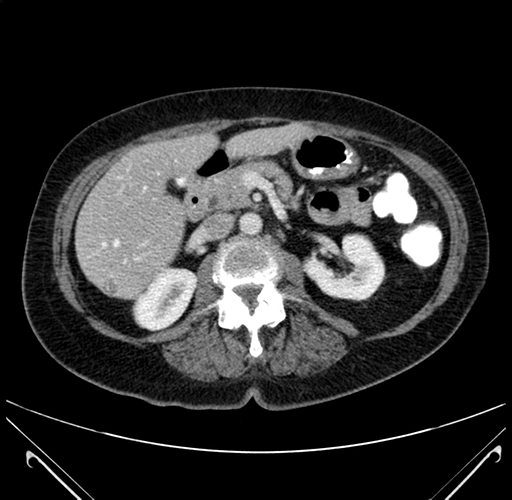

Pre-Chemo: Axial Venous

Axial Venous